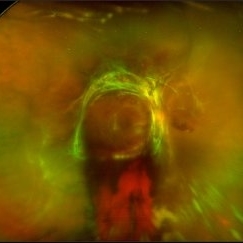

Von Hippel-Lindau Syndrome with Retinal Hemangiomas

Ultra-wide-field fluorescein angiogram of the left eye of an 29-year-old female with multiple retinal hemangiomas secondary to Von Hippel-Lindau Syndrome.

Photographer: Olivia Rainey

Imaging device: Optos California

Condition/keywords: fluorescein angiogram (FA), fluorescein leakage, left eye, Optos, retinal hemangioma, ultra-wide field imaging, Von Hippel-Lindau